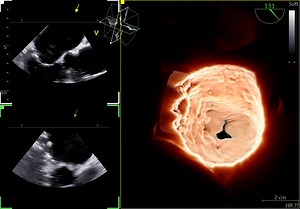

- TEE

Transducers - 3D TEE

Mitral MPR - Rebecca Hahn

Valve - What Is a 4D